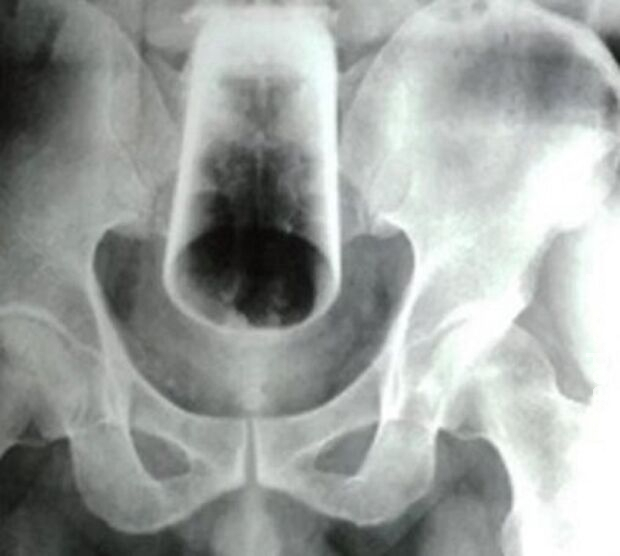

Homem precisou ser socorrido às pressas para um Hospital Regional da cidade de Cáceres, no Mato Grosso, após introduzir um copo de vidro no ânus.

No entanto, ao chegar ao local, a equipe percebeu a gravidade da situação, pois o copo havia quebrado dentro da parte intima do homem.

Diante da situação, o paciente foi encaminhado para o Hospital Regional, onde será submetido a uma cirurgia.